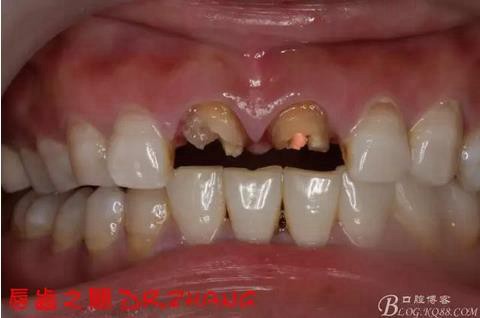

主訴:左上門牙腫脹數(shù)日

現(xiàn)病史:患者自訴兩年前在外院做了門牙的修復(fù) 一個月前左上門牙腫 服藥后消腫 前幾日腫脹厲害 影響正常生活 現(xiàn)來我院 要求治療

檢查:11 21金屬烤瓷冠 21根尖部牙齦紅腫 牙痛 叩(+++)冷刺激無反應(yīng) 11無不適癥狀 全口牙周情況良好

總結(jié):沒有術(shù)前照片 預(yù)備牙體過長 顏色還是有差距